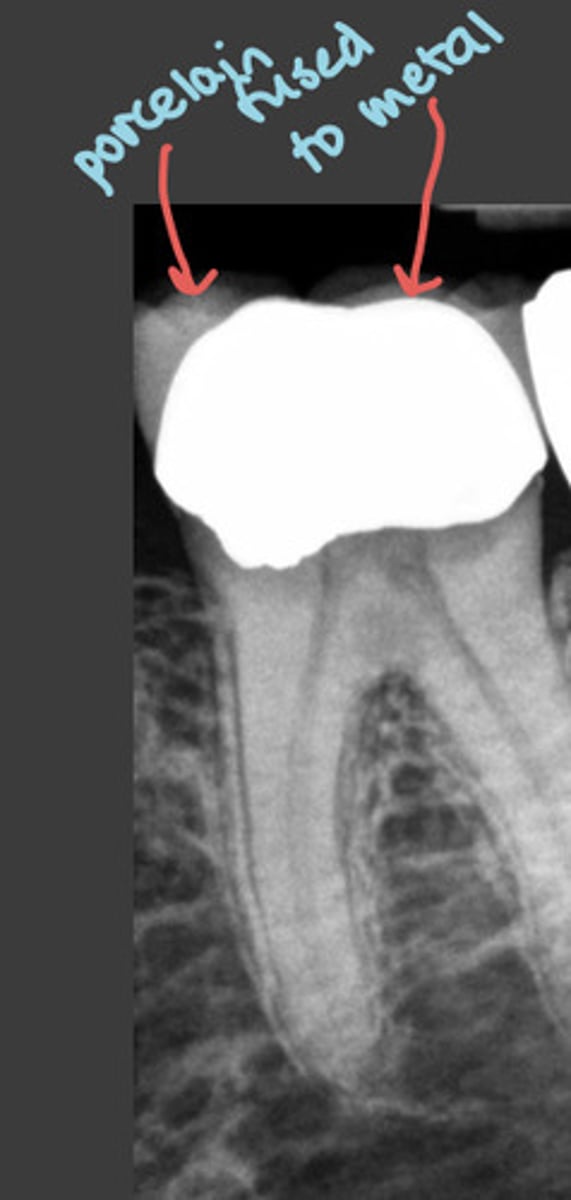

porcelain fused to metal crowns